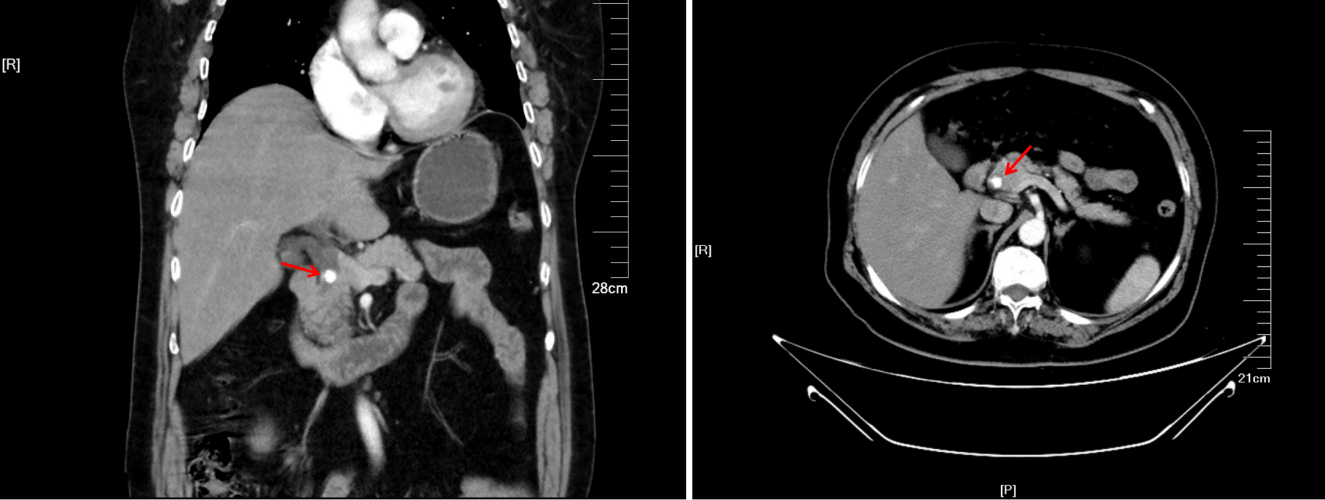

患者为62岁女性,因“发现右乳肿块2月余”收治于我院乳腺外科,入院后查CT提示:右乳腺癌;胆总管结石;胆囊结石。患者右乳腺癌合并胆道结石问题,经乳腺外科医师专科手术处理后,转肝胆胰外科进一步处理胆道结石。

▲CT 检查提示胆总管结石(红色箭头所示)